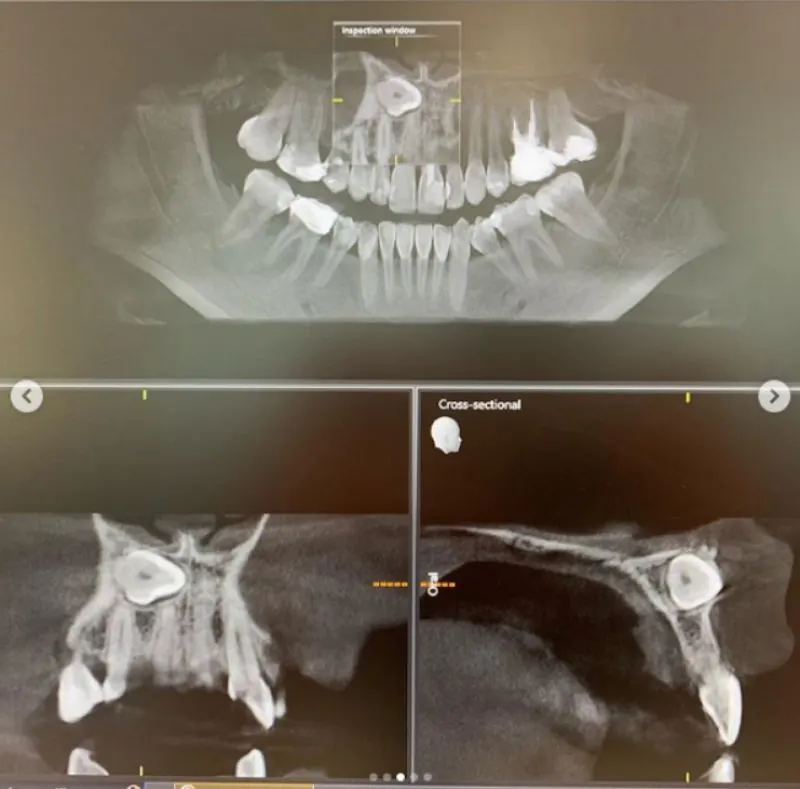

2 กรกฎาคม 2562 ไอจีที่ใช้ชื่อว่า b_boomm ได้โพสต์ภาพ นอนที่โรงพยาบาล สาเหตุฟังแล้วก็น่ากลัว สำหรับ บูม สุภาพร ดาราสาว และ พิธีกรดัง หลังพบว่ามีฟันคุด โผล่ตรงด้านหน้า ใกล้เส้นประสาท ตรงกลางหน้า เสี่ยงอันตราย จนต้องเข้ารับการผ่าตัด โดยมีทีมแพทย์ 2 และพยาบาลอีก 5-6 คน พร้อมข้อความระบุว่า…

เย้ ผ่าตัดเสร็จแล้ว ตื่นจากยาสลบเรียบร้อย ขอบคุณ @bdmswellness ที่ดูแลอย่างดี เคสบูม คือมีฟันคุดทางด้านหน้าใกล้เส้นประสาทตรงกลางหน้าเก็บไว้จะเป็นอันตรายอยู่ อาจจะเป็นถุงน้ำ หรือเนืองอกได้อีกด้วย และคลีนิคทั่วไปไม่สามารถผ่าออกได้ ทางคุณหมอดูแลอย่างดี วางยาสลบ ตื่นมาอีกทีก็ฟันไม่มีแล้วค่า เย้ ผ่าฟันที หมอสอง พยาบาลอีก5-6คน ไม่ธรรมดาจริงๆ ฮ่าๆ